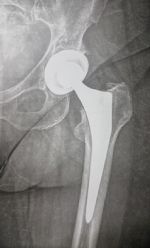

Το ισχίο ανήκει στις μεγάλες αρθρώσεις του κάτω άκρου και στις πολύ χρήσιμες για το βάδισμα και τις δραστηριότητες γενικότερα. Όταν εμφανιστεί πόνος ή περιορισμός στην κίνηση του ισχίου, θα πρέπει να ξεκουραστούμε και πάρουμε παυσίπονα και αν δεν ηρεμήσει θα πρέπει να επισκεφτούμε τον Ορθοπαιδικό.

ΠΑΘΗΣΕΙΣ ΙΣΧΙΟΥ